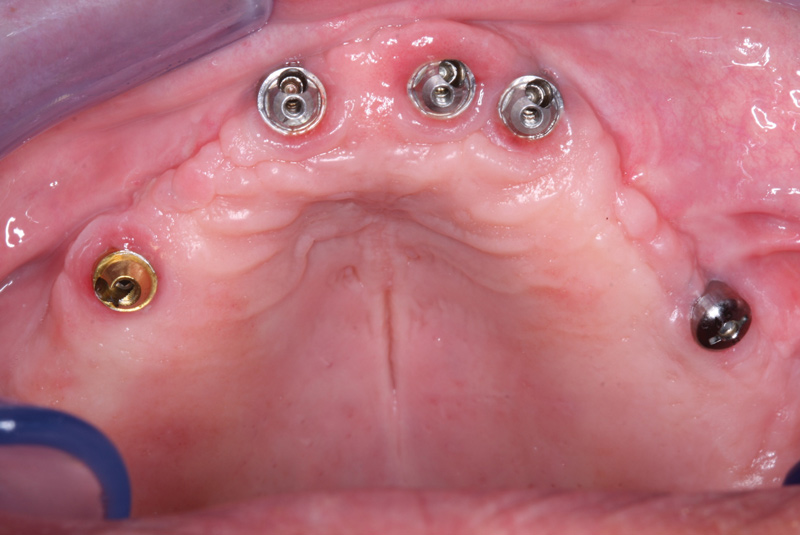

Fig 14. The failed implant site was curetted, and a new wider and longer implant was placed without osteotomy.

Figure 14

Immediate PMMA Retrofitting

A new computed tomography (CT) scan was taken to ascertain the location and amount of available bone and identify the location of the alveolar nerve. It was determined that the best approach would be curetting the failed implant site and placing a new, larger (ie, wider and longer) implant. All granulation tissue was curetted from the implant site and, without drilling an osteotomy, a new tapered implant was threaded into the site. The new implant must be placed within 20 degrees of the path of insertion of the existing prosthesis. The implant at No. 28 was not compatible with the full-arch zirconia protocol because of its restorative limitations, so the screw-retained abutment was removed and replaced with an implant cover screw to take this implant out of service for the restoration. (Figure 14).